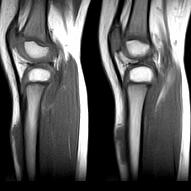

标题: PED0931:男,5岁,发现双小腿软组织肿块1年,质地中等,无 [打印本页]

标题: PED0931:男,5岁,发现双小腿软组织肿块1年,质地中等,无